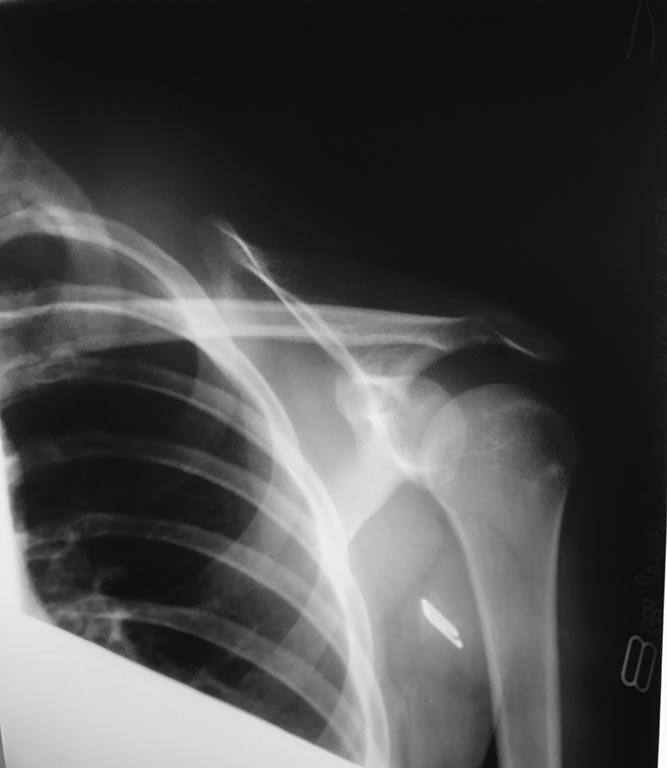

Многоуважаемые коллеги помогите советом. Обратилась девочка 15 лет с

болями в левом плечевом суставе,упала на лопатку. При клиническом

осмотре определяется асимметрия в положении лопаток(левая лопатка

располагается латеральнее и немного дорсальнее (более выпуклая) в

сравнении с правой),которая устраняется при сведении лопаток. Из

анамнеза известно, что первый аналогичный случай был после удара дверью

по лопатке. Тогда,со слов, в травматологическом отделении под общим

обезболиванием восстанавливался полный объём движений(непосредственно

вывиха плеча не было). А далее было несколько аналогичных случаев, но

лечение проводилось без хирургической тактики. Проходили обследование в

других клиниках, но толкового ответа нигде не услышали. Делали мрт

плечевого сустава, патологии не выявлено. Можно ли установить диагноз

привычный подвывих лопатки вследствие частичного повреждения мышц

плечевого пояса. Нестабильность левой лопатки? Какова тактика

действий,встречались ли вы с такими случаями?